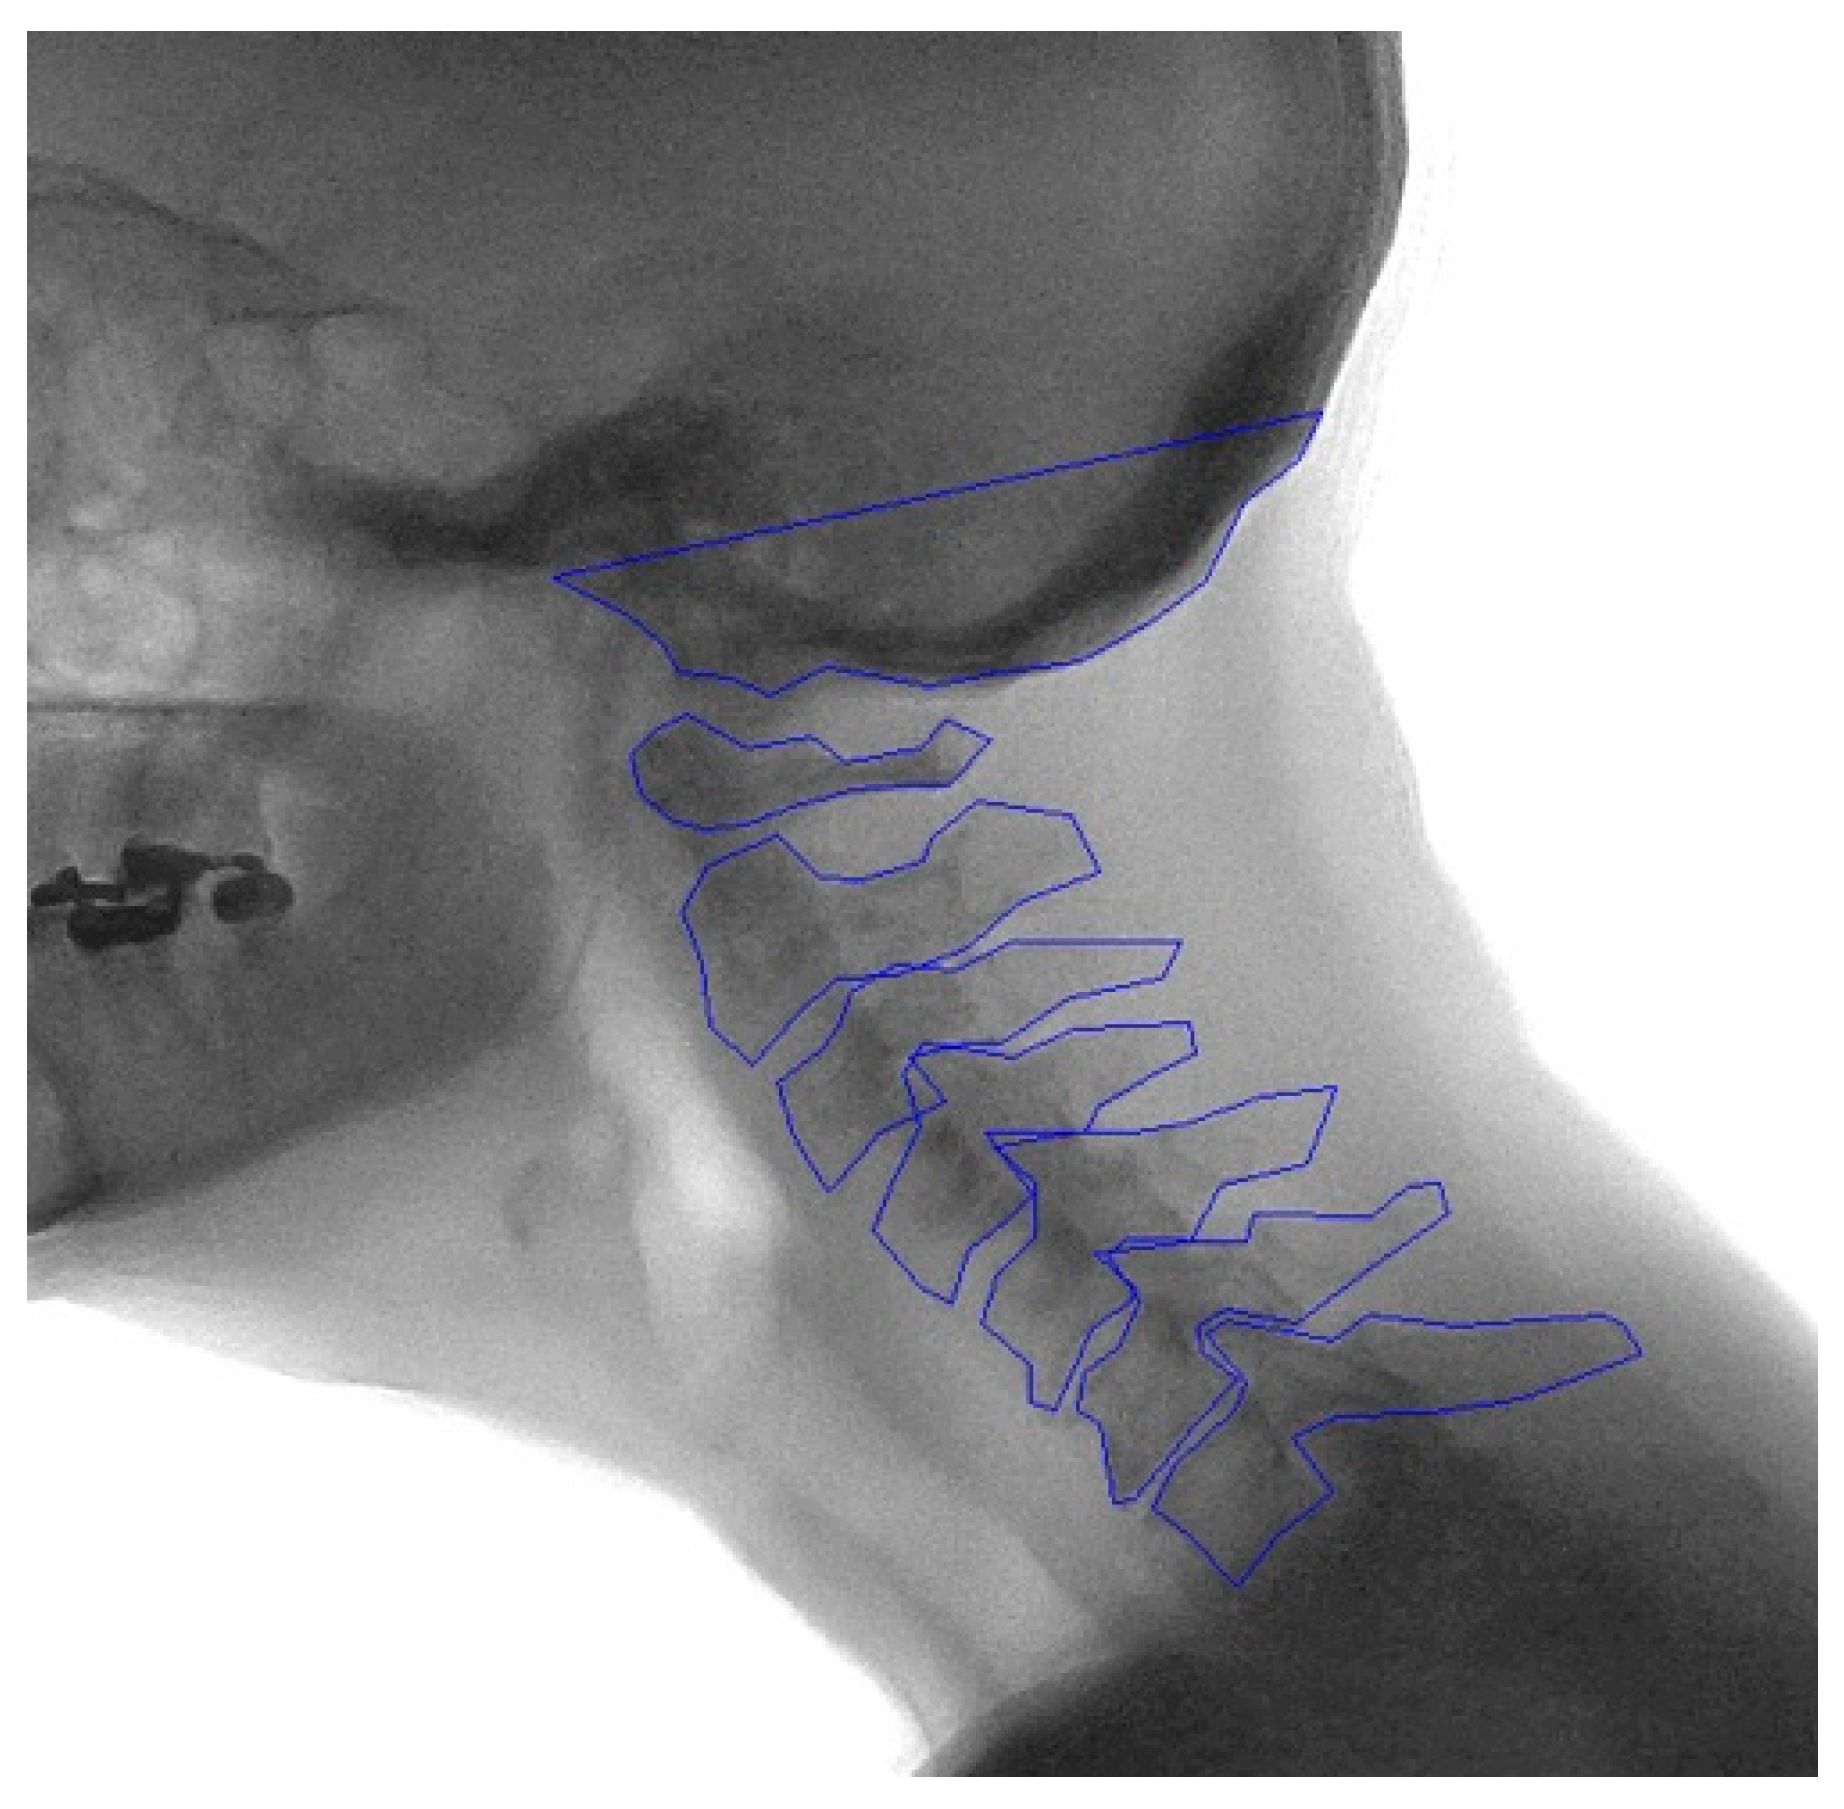

2.2. Manual Annotation

2.3. Development of the Model